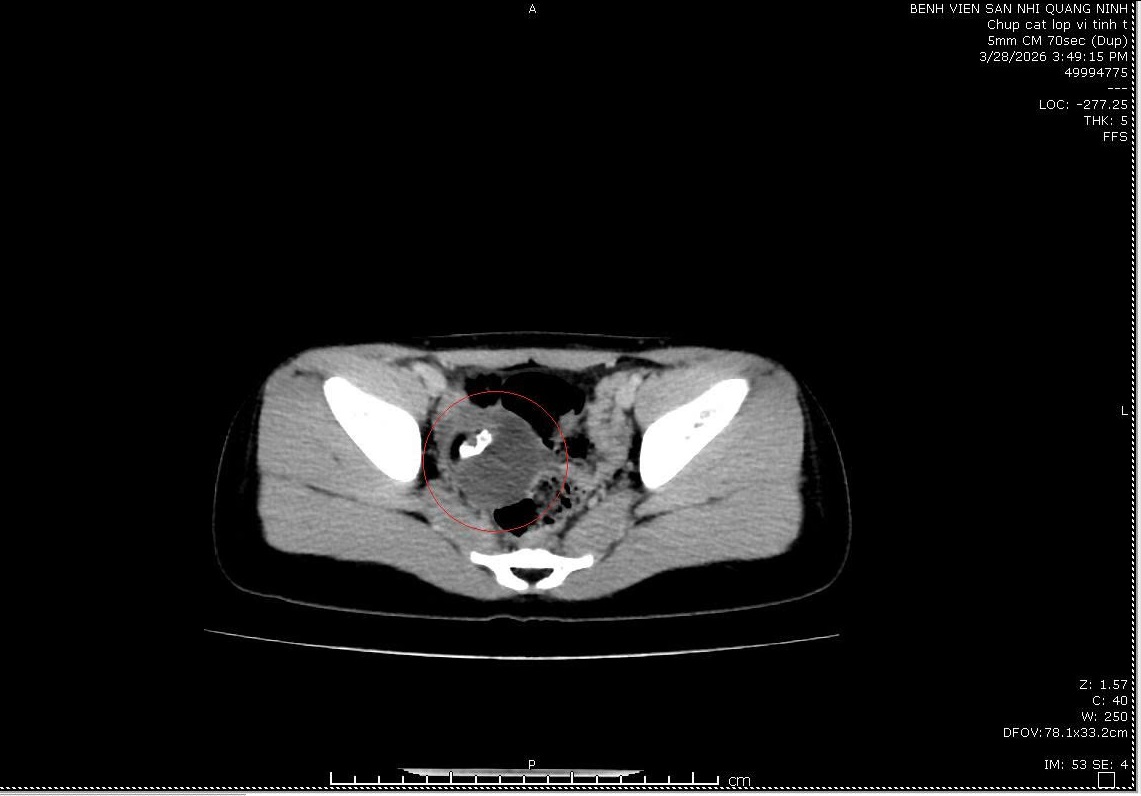

🩻Kết quả siêu âm, chụp cắt lớp vi tính cho thấy: Hình ảnh buồng trứng phải có khối dạng nang bì trong có tổ chức dịch, mô tỷ trọng dạng xương, KT 50 x 45 mm. Qua hội chẩn chuyên khoa các bác sĩ chẩn đoán U bì buồng trứng phải và chỉ định Phẫu thuật nội soi cắt u bì buồng trứng dưới gây mê nội khí quản cho bệnh nhân.

Với trường hợp bệnh nhi P.T.Tr (9 tuổi) do có khối u kích thước lớn (từ 5cm trở lên) nên cần phải tiến hành phẫu thuật. Bởi nếu để muộn, rất dễ xảy ra tình trạng xoắn cuống khối u, vỡ khối u, chèn ép các cơ quan xung quanh… Trong trường hợp này, các bác sĩ đã khéo léo loại bỏ khối u và bảo tổn buồng trứng cho bệnh nhi 9 tuổi.